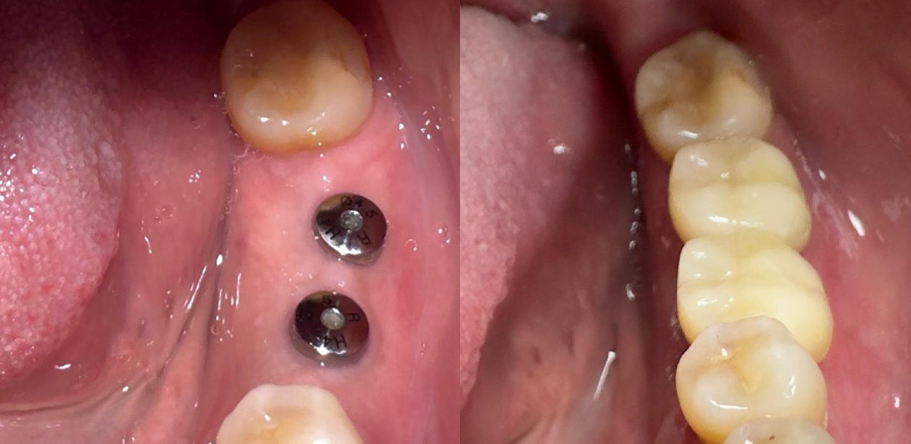

Antes

Después